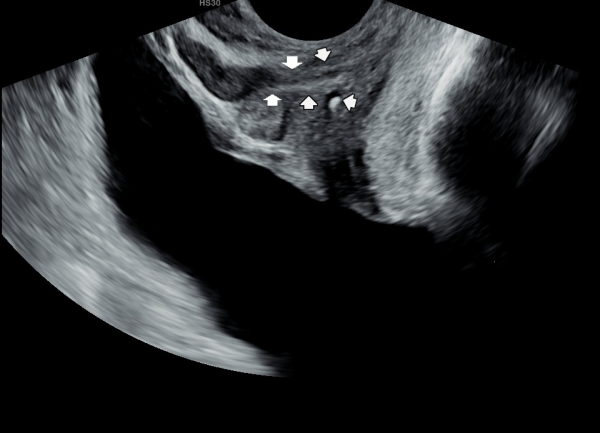

수년전 배뇨장애와 야간 빈뇨 그리고 가슴이 답답하다고 내원 당일 검사한 경직장 전립선 초음파 사진(160/100 - 99-81Kg)

사정관내 탈락된 상피 세포 덩어리가 군데 군데 관찰되고 쌓여서 사정관 입구와 전립선 관 등에 결석을 형성하고 있는 자료입니다.

Transrectal prostate ultrasound image taken on the day of visit due to several years of voiding difficulties, nocturnal frequency, and chest tightness (160/100/99–81kg).

Clusters of desquamated epithelial cells are observed in various areas within the ejaculatory ducts, accumulating to form stones at the ejaculatory duct orifices and within the prostatic ducts.